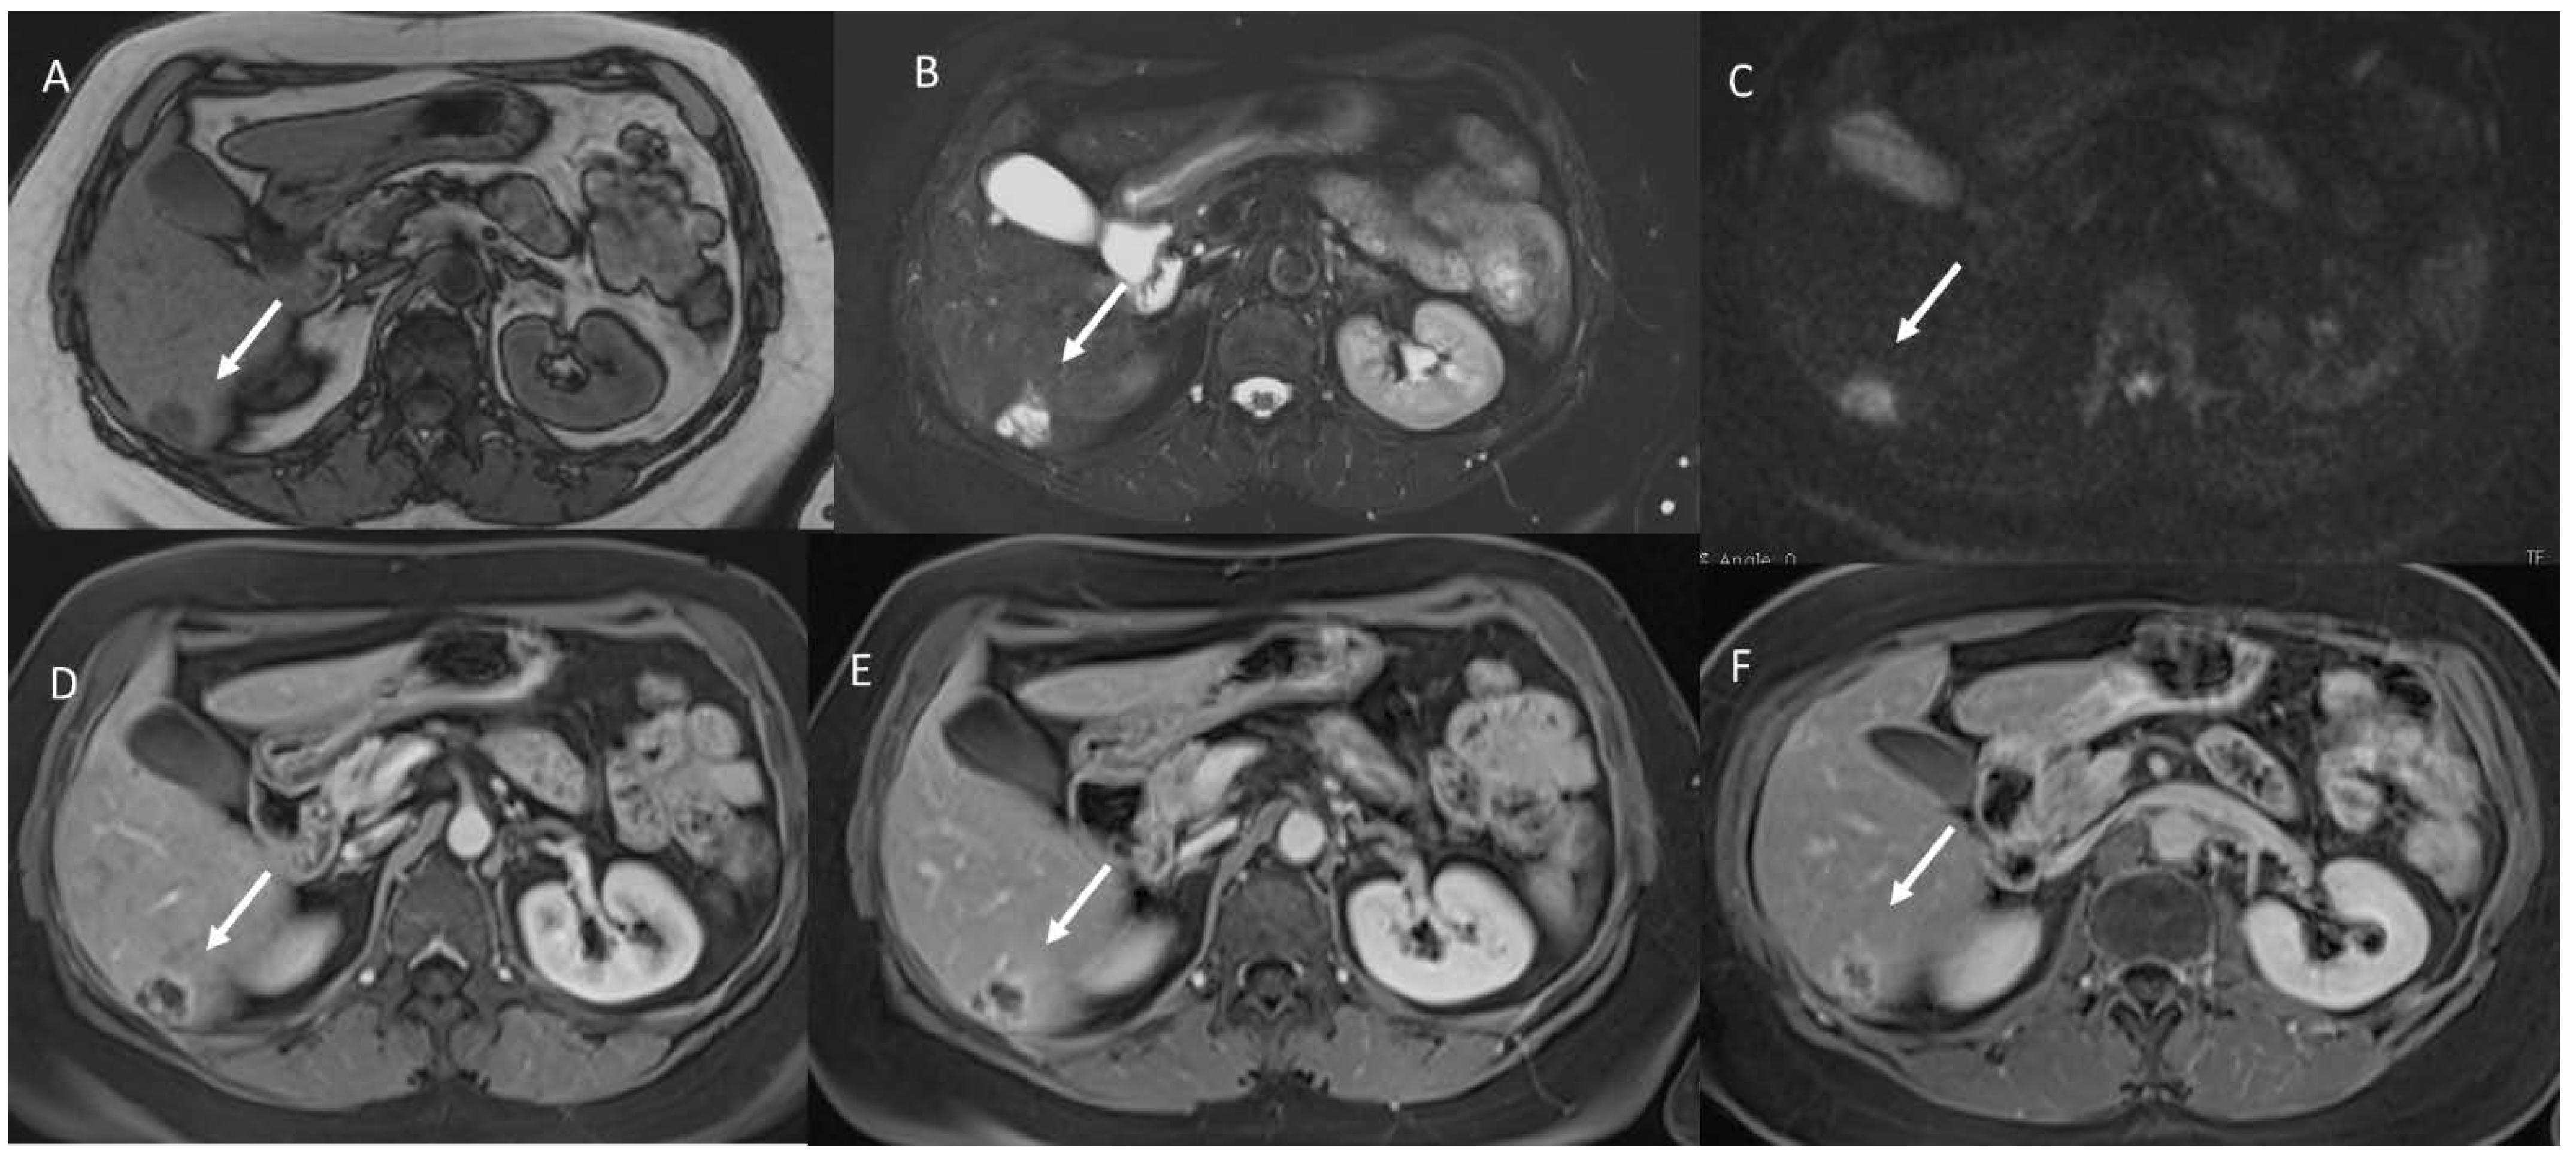

Figure 6. Cholangiocarcinoma patient, classified as LR-M according to LI-RADS, due to targetoid appearance (arrow) in T2-W (A) sequence, in (B) DWI, and (C) late phase of contrast study.

At the highest level, SR has all the previously mentioned features and uses a standardized language, based on a universally accepted lexicon [9,85,86]. A significant example in the field of breast imaging, is the breast imaging reporting and data system (BI-RADS), promoted by the American College of Radiology (ACR). BI-RADS includes a standardized lexicon for the description of breast imaging findings and their clinical management [15]. Like BI-RADS, in order to standardize the reporting and interpretation of imaging data, similar approaches have been introduced for different lesions, such as liver lesions, thyroid lesions, prostate lesions, and nodal evaluation [30]. Regarding HCC, the Liver Imaging Reporting and Data System (LI-RADS) represents a way of interpreting and reporting radiological findings that were obtained by CT or MRI, in patients at risk for this tumor. Despite the introduction of a new category, LR-M extends this system to other lesions, such as cholangiocarcinoma (Figure 6) and metastases. The American College of Radiology (ACR) supported the spread of LI-RADS to homogenizing the interpreting and reporting data of liver lesions. The diagnosis of hepatocellular carcinoma is due to the presence of important imaging features, which allow us to classify LI-RADS-3, LI-RADS-4, and LI-RADS-5, and to include arterial-phase hyperenhancement, tumor diameter, wash-out appearance, capsule appearance, and threshold growth. Ancillary features are features that can be used to change the LI-RADS classification. In MRI studies, ancillary features that support malignancy can be used to update the category of one or more categories, but not beyond LI-RADS-4 [30].